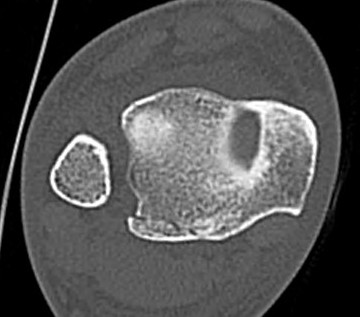

CT

Normal bilateral axial CT

Bilateral axial CT

- compare to other side

- widening

- malrotation

- posterior malleolar fracture / Volkmann tubercle

- anterior tubercle / Tillaux-Chaput tubercle

Gifford's tibiofibular line (TFL)

- anterolateral fibula

- should be < 2 mm from tibia

< 4 mm Tibio-fibular gap

Normal Gifford's line and tibiofibular gap

Abormal Gifford's line and increased tibiofibular gap with posterior malleolar fracture

Tillaux-Chaput fracture on right with mild increased widening